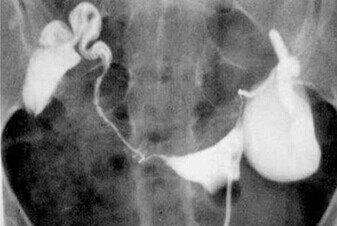

关于输卵管积水对IVF妊娠结局的影响,研究结果显示,输卵管积水使IVF-ET 的着床率及妊娠率降低、流产率增加,主张先处理输卵管积水再进行IVF-ET,一般选择手术治疗。目前学术界对输卵管积水手术方式的选择意见不一,常用的手术方式有经阴道超声下输卵管积水抽吸术、输卵管切除术、输卵管伞端或壶腹部造口术、输卵管近端结扎术等,以及近年来开展的输卵管栓塞术等。

1、经阴道超声下输卵管积水抽吸术,其机制可能是降低了输卵管压力,防止积水流向宫腔,避免输卵管积水的液体对胚胎的毒性作用。但是此法易使输卵管积水复发,故有时需多次穿刺抽吸。

2、近年来,学术界提倡以切除积水严重的输卵管作为IVF-ET前的首选处理方式。Verhulst等在1994年报道切除积水的输卵管不会影响卵巢功能,且可能更易监测卵泡发育,其临床妊娠率明显高于术前。此后相似的报道不胜枚举。但也有大量研究认为,输卵管切除术可能会破坏同侧卵巢的血供,影响该侧卵巢激素的分泌以及卵泡发育,故输卵管切除术并非最佳方案。

3、一些研究者主张在输卵管积水不严重的情况下应尽量保留卵巢功能,可在腹腔镜或开腹手术下行输卵管伞端或壶腹部造口术,此术式保留了输卵管,避免影响同侧卵巢血供和卵泡发育,胚胎移植的妊娠率亦可提高,缺点是有可能出现异位妊娠,个别患者输卵管积水会复发。

4、输卵管近端结扎术 有研究称输卵管近端结扎术与输卵管切除术对卵巢血供的影响及对患者IVF结局的影响无显著差异性,而有学者提出输卵管近端结扎、远端造口手术和腹腔镜输卵管切除术并不减弱卵巢的超排卵反应,故可作为IVF-ET前处理输卵管积水的主要选择。

5、此外,最新的研究显示,输卵管栓塞术与其他传统4种术式比较具有简便、安全、经济的特点,不但不影响卵巢功能,还可显著增加临床妊娠率、杜绝输卵管妊娠的发生,具有良好的应用前景。